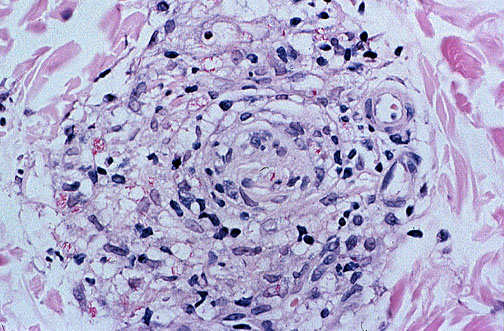

| Fite's modification of the acid fast stain reveals single thin short red rods of M. leprae, as well as some clusters of organisms in macrophages. In the tuberculoid form, acid fast organisms are hard to find, but in the lepromatous form, there are macrophages filled with numerous acid fast bacilli ("globi"). Seen here is the "borderline" form with some organisms and some epithelioid cells. It is now possible to control leprosy with drug therapy (rifampin as a first-line drug and dapsone second). |